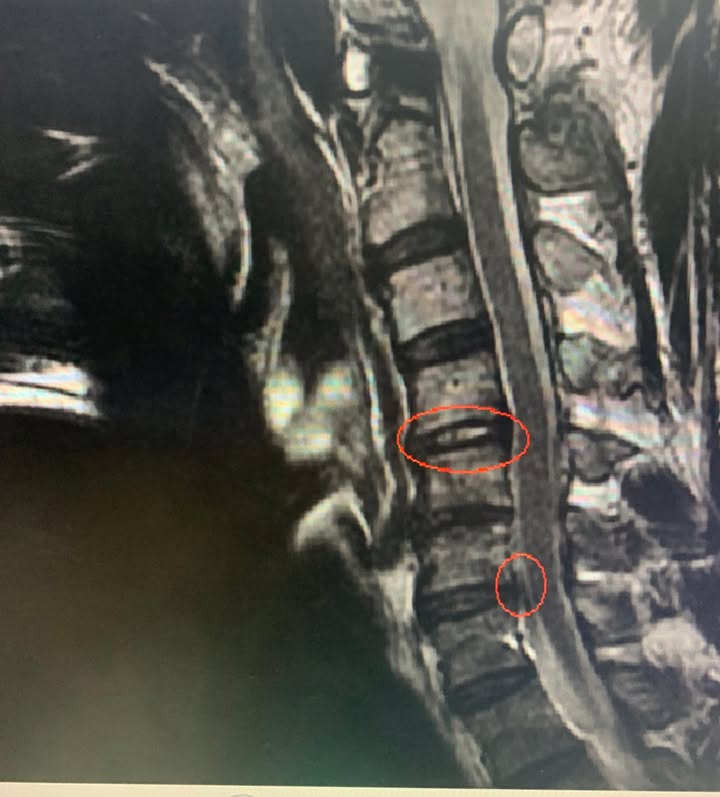

Cervical Spine Treatment Cases 頸椎治療案例 😂原本都準備要去開刀了! 😢醫學中心報價兩節椎間盤報價52萬 😄感謝苗栗患者熱情見證... 2019.11.22 ❇️頸椎間盤突出痛到完全無法洗頭 #核磁共振證實C4C5突出壓迫 #上樓梯頭往後面抬就誘發... 2019.11.13 #頸椎痛到無法睡覺怎麼回事 #原本認真考慮開刀治療 #感謝雲林患者熱情北上見證 #脊椎... 2019.10.21 #原本都要安排開刀結果逆轉勝 #脊椎整合中醫微創療法奏效 #感謝宜蘭黃大哥熱情見證 2019.08.24 #頸椎痛連肩膀是怎麼回事 #核磁共振證實頸椎神經根卡壓 ✨頸椎整合中醫微創立大功有奇... 2019.07.24 #外傷後長達十年胸悶胸痛醫案 #脊椎整合中醫微創療法 #感謝林先生熱情見證 2019.07.20 #頸椎間盤多節斷坍塌跟突出案例 #頸椎中醫超微創療法奏效 #曾經右肩膏肓麻痛到上臂無... 2019.07.18 #衝浪族小心頸椎椎間盤突出啊 #兩分鐘瞭解神經根型頸椎病 #感謝宜蘭于大哥熱情帥氣見... 2019.07.17 #膏肓疼痛是怎麼回事 #神經根型頸椎病 #五次治療大幅度改善 2019.07.11 #神經根型頸椎病 #五次治療提前畢業 2019.07.03 #頸椎壓迫神經根醫案分享 #冷熱知覺消失合併握力嚴重衰退 #頸椎整合針刀醫學療法如何... 2019.05.31 #神經根型頸椎病醫案 #頸椎痛連上臂怎麼辦 #一張圖秒懂超微針刀療法如何處理骨刺 2019.05.22 #長達十年肩頸痛連手臂曾經痠痛到手無力無法做事情 #神經根型頸椎病是什麼 #不想開刀... 2019.03.12 #頸椎間盤嚴重突出醫案 #一張圖秒懂為何中醫超微針刀有效原理 #脊椎整合超微針刀療法 2019.03.01 #頸椎痛到半夜麻醒一年醫案 #身為一個女性患者聽到針刀反應如何⁉️有關頸椎針刀整合門... 2019.02.21 ← 上一頁 7 8 9 10 下一頁 →